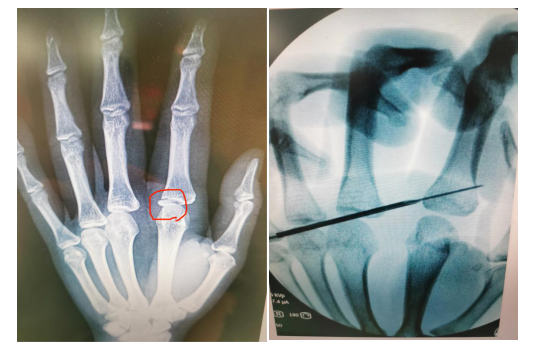

前几日的一个凌晨,伴随着一阵急促的脚步声,一对中年人带着一个10多岁的男孩来到了急诊科,孩子的妈妈急切的问到:“医生,快看看我孩子的手指在学校打架骨折了,能不留疤吗,他以后还要去当兵呢!”接诊的唐医生看了他们带来的X线光片:右示指近节指骨基底部尺掌侧累及关节面的小骨折,复位起来比较困难,尤其是闭合复位更是困难。但是考虑到孩子以后想要当兵的心愿,唐医生手术团队,决定给孩子利用1号针头,制作套筒,在C臂机透视下做了闭合复位内固定,骨折达到了解剖复位。

唐洪伟医生说:这个手术要想做闭合复位难度比较大,令人头疼。主要是骨块在掌侧累及关节面,闭合复位困难较大,不好撬拨,而且骨折累及关节面,我们用1号针头作为套筒,可以非常方便的进行撬拨复位,位置满意后,将克氏针顺着套筒固定骨折端,创伤非常小,没有缝针,术后拔除克氏针后,无任何疤痕。实现了真正的微创手术。